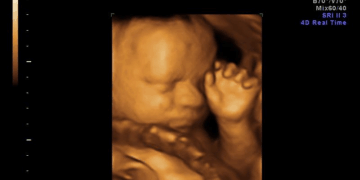

Many in our society argue that abortion is acceptable because unborn babies are not yet fully conscious. Society seeks to devalue the lives of the unborn, creating its own definitions of humanity based on distorted views of morality. But the…